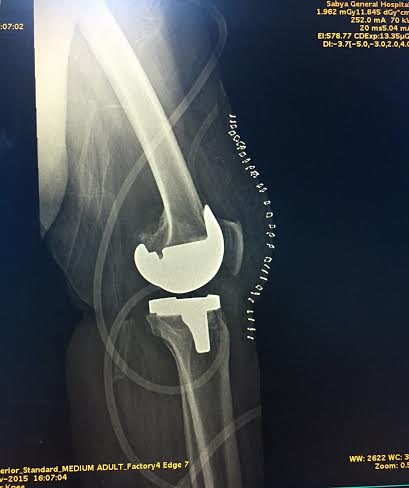

نجح فريق طبي بمستشفى صبيا العام في إنهاء معاناة مريضة سبعينية كانت تعاني من صعوبة في الحركة بسبب التهاب في مفصل الركبة؛ وذلك من خلال إجراء عملية لتركيب مفصل صناعي للركبة.. وتُعَد هذه العملية هي الثانية من نوعها على مستوى مستشفيات منطقة جازان.

وأوضح رئيس الفريق الطبي استشاري العظام الدكتور محمد بن علي الحازمي، أن المريضة كانت تعاني من آلام متواصلة في الركبة، وبعد خضوعها لعدد من الفحوصات الإشعاعية والمخبرية، تَبَيّن أنها تعاني من التهاب في مفصل الركبة كان يسبب لها صعوبة في الحركة ويزيد من شعورها بالآلام؛ خصوصاً أن المسكنات والأدوية لم تعد قادرة على إسكان الألم.

لذا تَقَرّر تركيب مفصل صناعي للركبة لإزالة معاناتها التي لازمتها منذ فترة طويلة حسب إفادتها.

وبيّن أنه جرى تشكيل فريق طبي متكامل من أطباء تخدير وطاقم تمريض من المستشفى؛ من أجل توفير رعاية طبية متكاملة للمريضة قبل وأثناء وبعد العملية، وبعد أن تم تأمين المفصل الصناعي الحديث ذي الجودة والمرونة العالية من قِبَل شركة “سترايكر”، تم تنويمها وإجراء العملية التي تكللت بالنجاح ولله الحمد.

وأكد “الحازمي” أن هذه العملية الفريدة من نوعها على مستوى مستشفيات منطقة جازان تأتي استمراراً للتطور في الرعاية الصحية التي تشهدها كل الأقسام العلاجية بمستشفى صبيا، وكفيلة بإحداث نقلة نوعية في جراحة العظام التي تساعد العديد من المرضى الذين يعانون من الآلام الشديدة والمستمرة في مفصل الركبة، وتزيل عنهم عناء التنقل بين المناطق الأخرى بحثاً عن العلاج؛ خصوصاً أن هذه العملية تُعَدّ الثانية التي أجريت بمستشفى صبيا قبل بضعة أشهر، والتي تَكَلّلت حينها بالنجاح؛ مقدماً شكره لمدير المستشفى الدكتور عيسى بن لاحق دلاك الذي يسخّر كل الإمكانيات ويذلل كل العوائق للارتقاء بالخدمات الصحية لمرضى ومراجعي مستشفى صبيا العام.